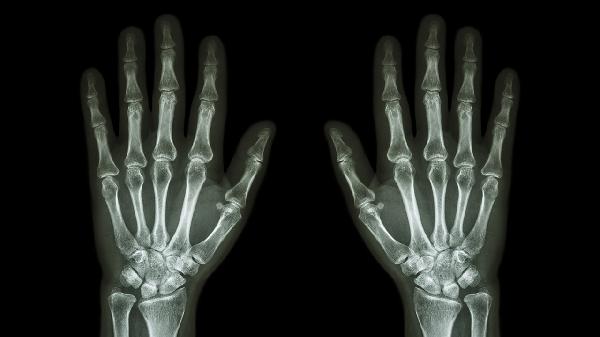

无名指关节受到外力撞击或扭伤可能导致关节肿痛。外伤引起的关节肿痛通常伴有皮下淤血、压痛明显,轻微活动时疼痛加剧。急性期可进行冷敷缓解肿胀,后期热敷促进血液循环。若疼痛持续不缓解,可能存在骨折或韧带损伤,需进行X线检查。